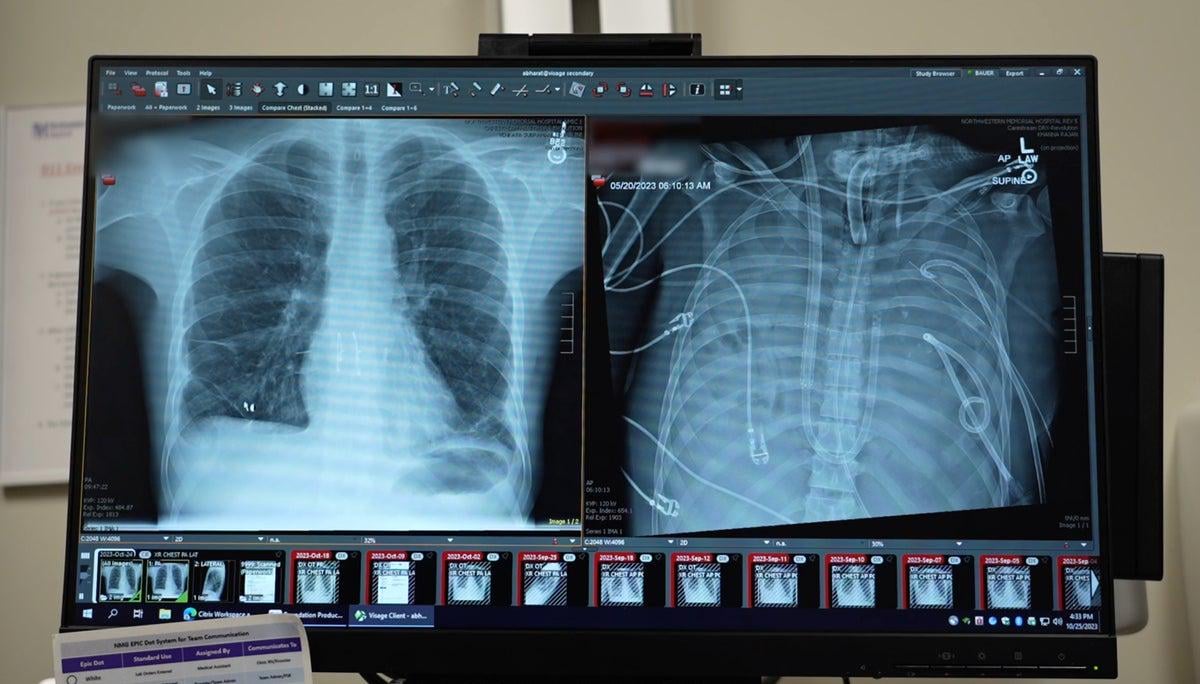

In 2023 thoracic surgeon Ankit Bharat was working at Northwestern Memorial Hospital when he was drafted to help a 33-year-old influenza patient who was on the verge of death. The sick man needed a double-lung transplant, but there was a problem: he was too sick for Bharat and his colleagues to attempt the operation.

So Bharat and his team worked up a plan: They would build an “artificial lung” that could help pump blood from the right side of the patient’s heart to the organ’s left side, oxygenate it and send it on to the rest of the body. The system kept the patient alive for two days, enabling him to begin to recover from the infection. Now, more than two years later, “he’s doing great, by the way,” Bharat says.